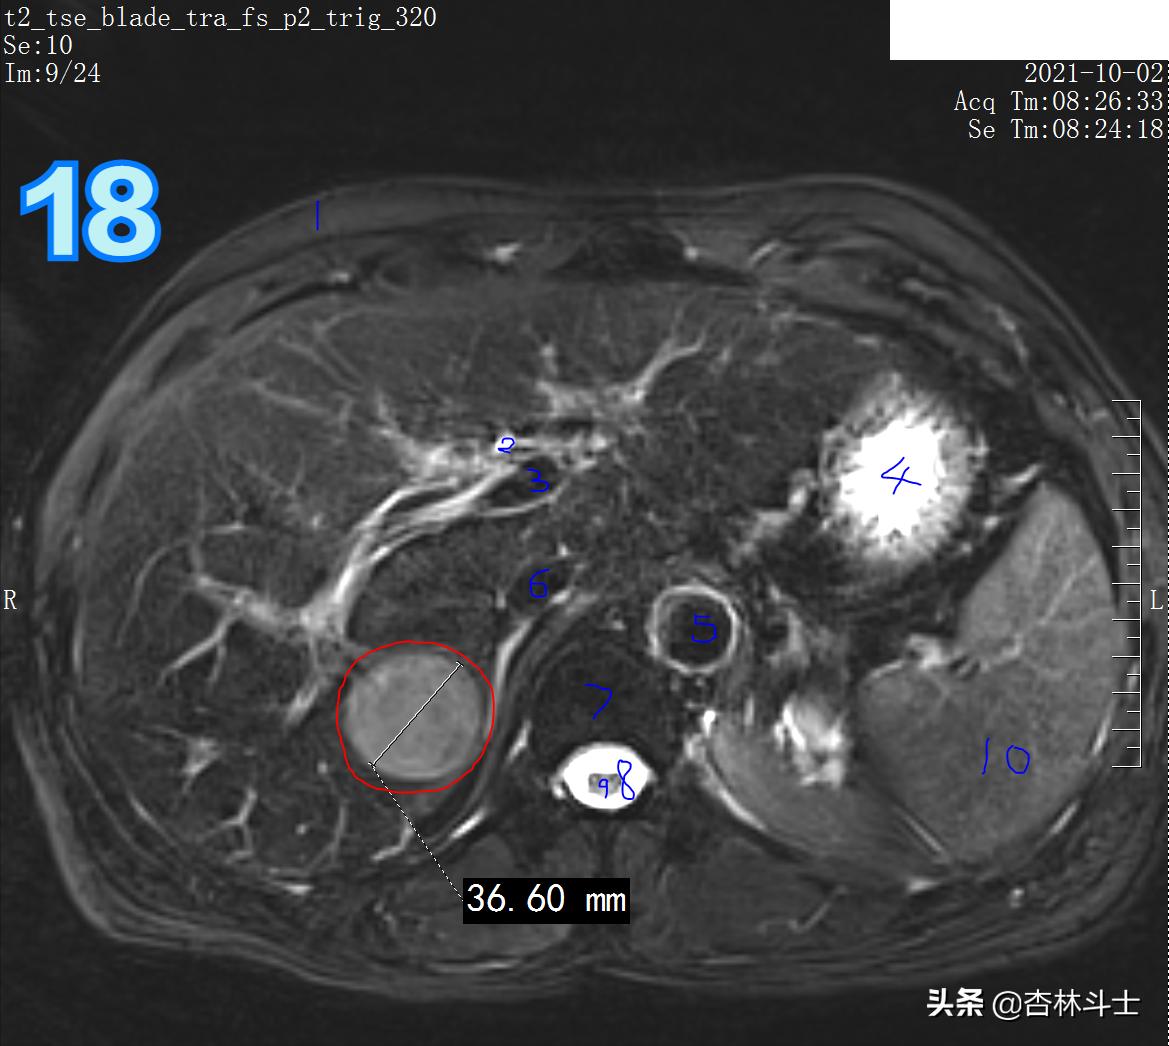

T2压脂

图18 1、皮下脂肪 2、肝内胆管 3、肝内门静脉分支 4、胃 5、腹主动脉 6、下腔静脉 7 椎体 8、椎管 9、脊髓 10 脾

DWI

图19、20 病灶弥散明显受限。